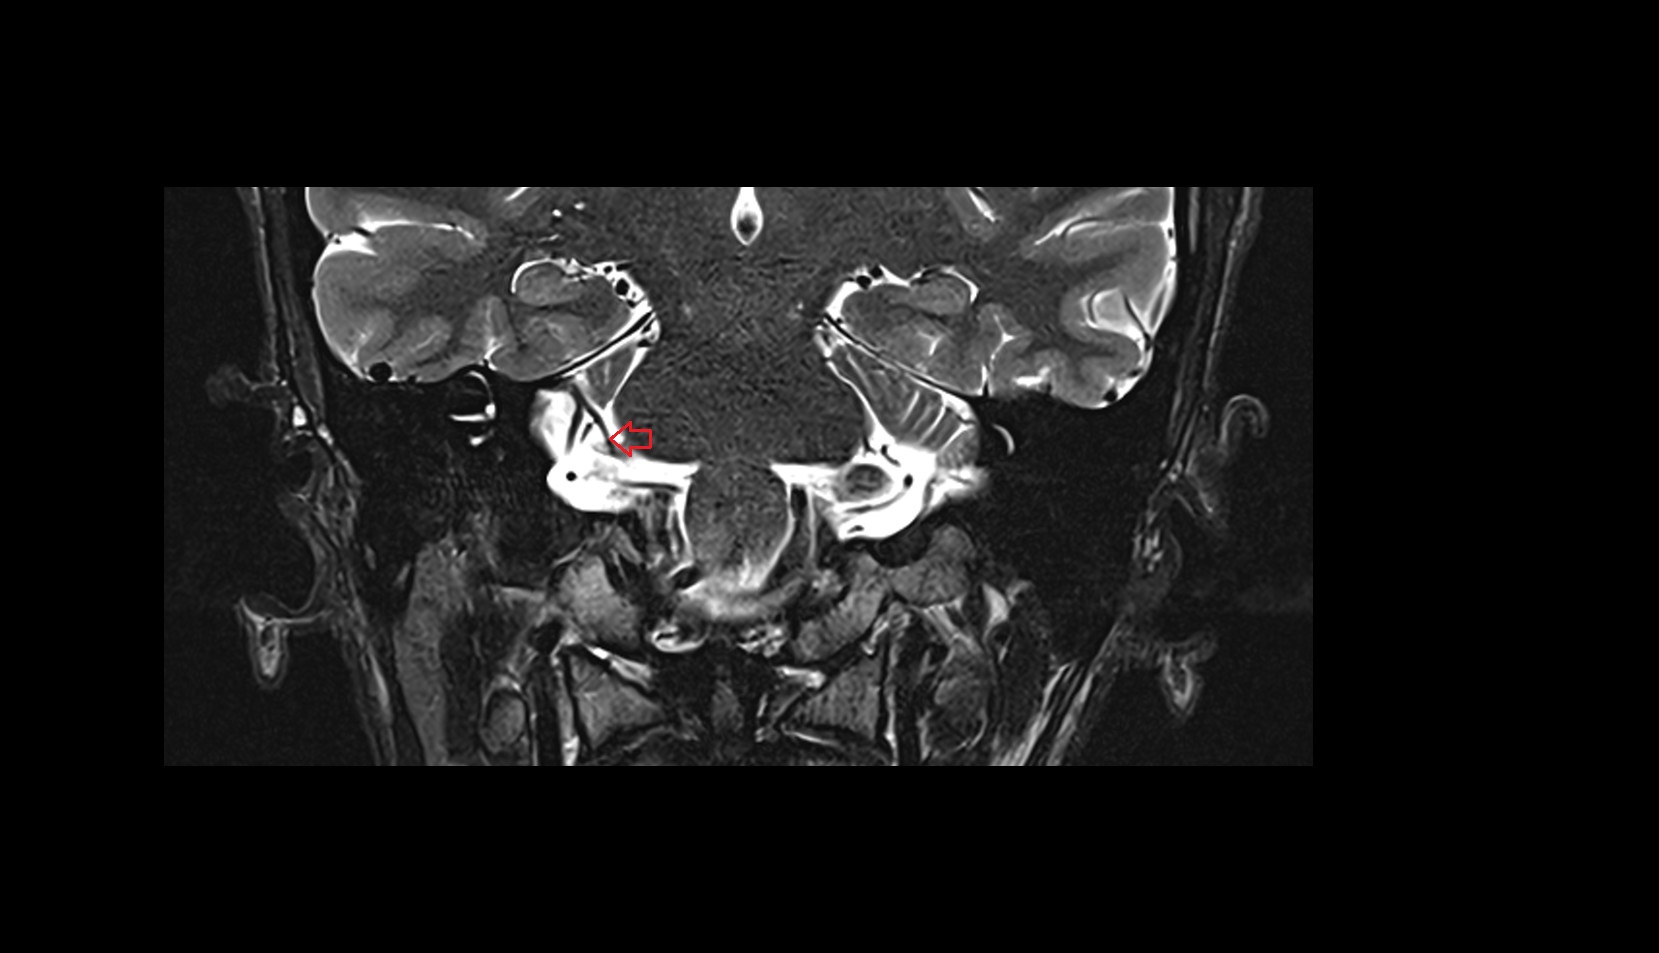

- Lateral aperture of fourth ventricle (foramen of Luschka)